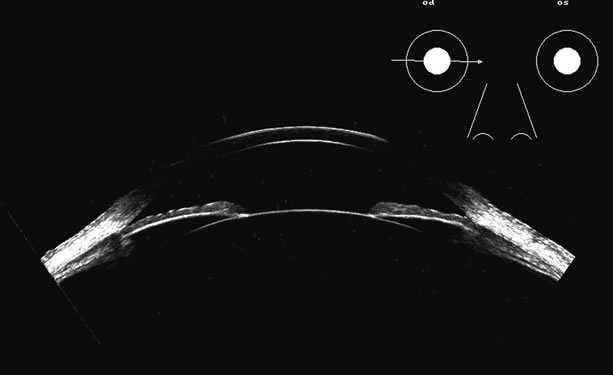

Lens position, presence, and integrity can be shown most easily with immersion ultrasound, since the proximity of these structures to the transducer in contact techniques makes them difficult to display. Immersion or a water standoff makes it possible to visualize the anterior segment by moving the “noise” of the main bang of the transducer forward, away from the structures of interest and the focal zone onto this area.8 The lens is a “specular” reflector which, like the cornea, is a smooth, highly reflective surface. Whereas specular reflectors, such as the lens, may deflect most acoustic energy away from the transducer when insonified at an oblique angle, “diffuse” reflectors, such as blood-covered membranes, are more easily discerned on B-scan. Blood enhances lens boundaries; that is, it converts the specular reflective surface to a diffuse reflective surface, making the entire outline of the surface more easily seen, even at regions angled so they would otherwise deflect the returning echoes away from the transducer and not be identifiable. The posterior capsule is concave and thus perpendicular to the beam over much of the arc of sector B-scanning, thus making it always easy to identify. The lens outline should be smooth and unbroken (Fig. 1); a damaged lens often is cataractous and has internal echoes as well as interrupted surface echoes.9 Kinetic scanning, that is, real-time scanning while the patient moves his or her eye, can be used to check for mobility of the lens in dislocated or partially dislocated lenses.